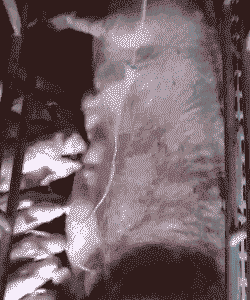

如果母猪产后出现严重病状,如发烧、不食、肌肉注射无法缓解,那么可以考虑输液治疗。输液分为静脉输液和腹腔膜输液两种,后者药量较大,吸收不如静脉好,但操作方便。